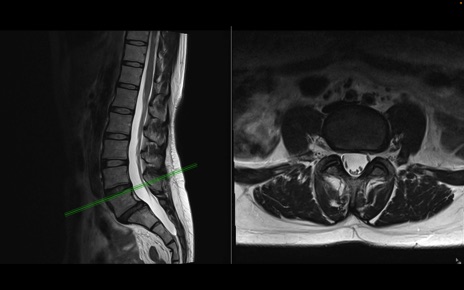

腰椎MRI

T2WI(横断像)

T2WI(矢状断像)